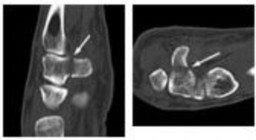

. - الأشعة المقطعية (CT Scan): توفر صوراً تفصيلية ثلاثية الأبعاد للعظام، وهي مفيدة جداً لتقييم الكسور المعقدة، مثل كسور العظم الخطافي (Hamate Hook Fracture) التي قد لا تظهر في الأشعة السينية العادية

، أو لتقييم مدى تدهور العظم في حالات مثل مرض كينبوك. - التصوير بالرنين المغناطيسي (MRI): ممتاز لتقييم الأنسجة الرخوة مثل الأربطة، الأوتار، الأعصاب، والعضلات. يكشف عن التمزقات،